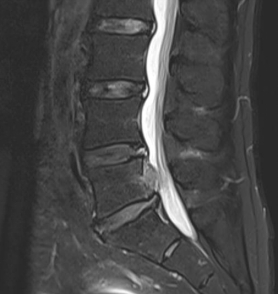

作为目前骨科领域领先的脊柱微创技术,UBE技术通过建立两个直径仅0.5—0.7cm的微小通道,将内镜、操作器械分别置入。医生可通过高清内镜画面,清晰观察脊柱内部的病变组织——无论是突出的椎间盘、狭窄的椎管,还是增生的骨赘,都能在放大视野下一目了然。相较于传统开放手术,UBE技术实现了“小切口解决大问题”:术中出血极少,创伤面积不足传统手术的1/5,术后疼痛轻,患者可快速下床活动,住院时间缩短至3—5天,极大降低了术后感染、粘连等并发症风险,尤其适用于腰椎间盘突出症、腰椎管狭窄症等常见及复杂脊柱疾病,让脊柱治疗告别“大动干戈”,迈入微创精准诊疗时代。

如果说UBE技术是脊柱治疗的“精准镜手”,那么3D打印技术就是定制化治疗的“私人裁缝”。针对每一位脊柱疾病患者的个体差异,医生通过高精度CT扫描,获取患者脊柱的三维立体数据,利用3D打印技术1:1还原脊柱的解剖结构——从椎体形态、椎间盘位置,到神经走行、病变范围,都能精准复刻,形成专属的脊柱模型。基于此模型,医生术前可以进行精准规划:模拟手术路径、预判操作风险、选择适配的内固定器械,甚至打印定制化的椎间融合器、内固定支架,确保手术操作“有的放矢”,贴合患者的个体解剖特征,避免传统手术中“凭经验操作”的不确定性,让脊柱治疗从“标准化”走向“个性化”,极大提升了手术的精准度与安全性。